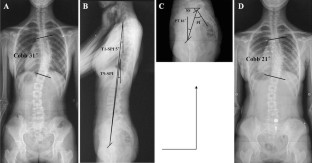

Fig. 2